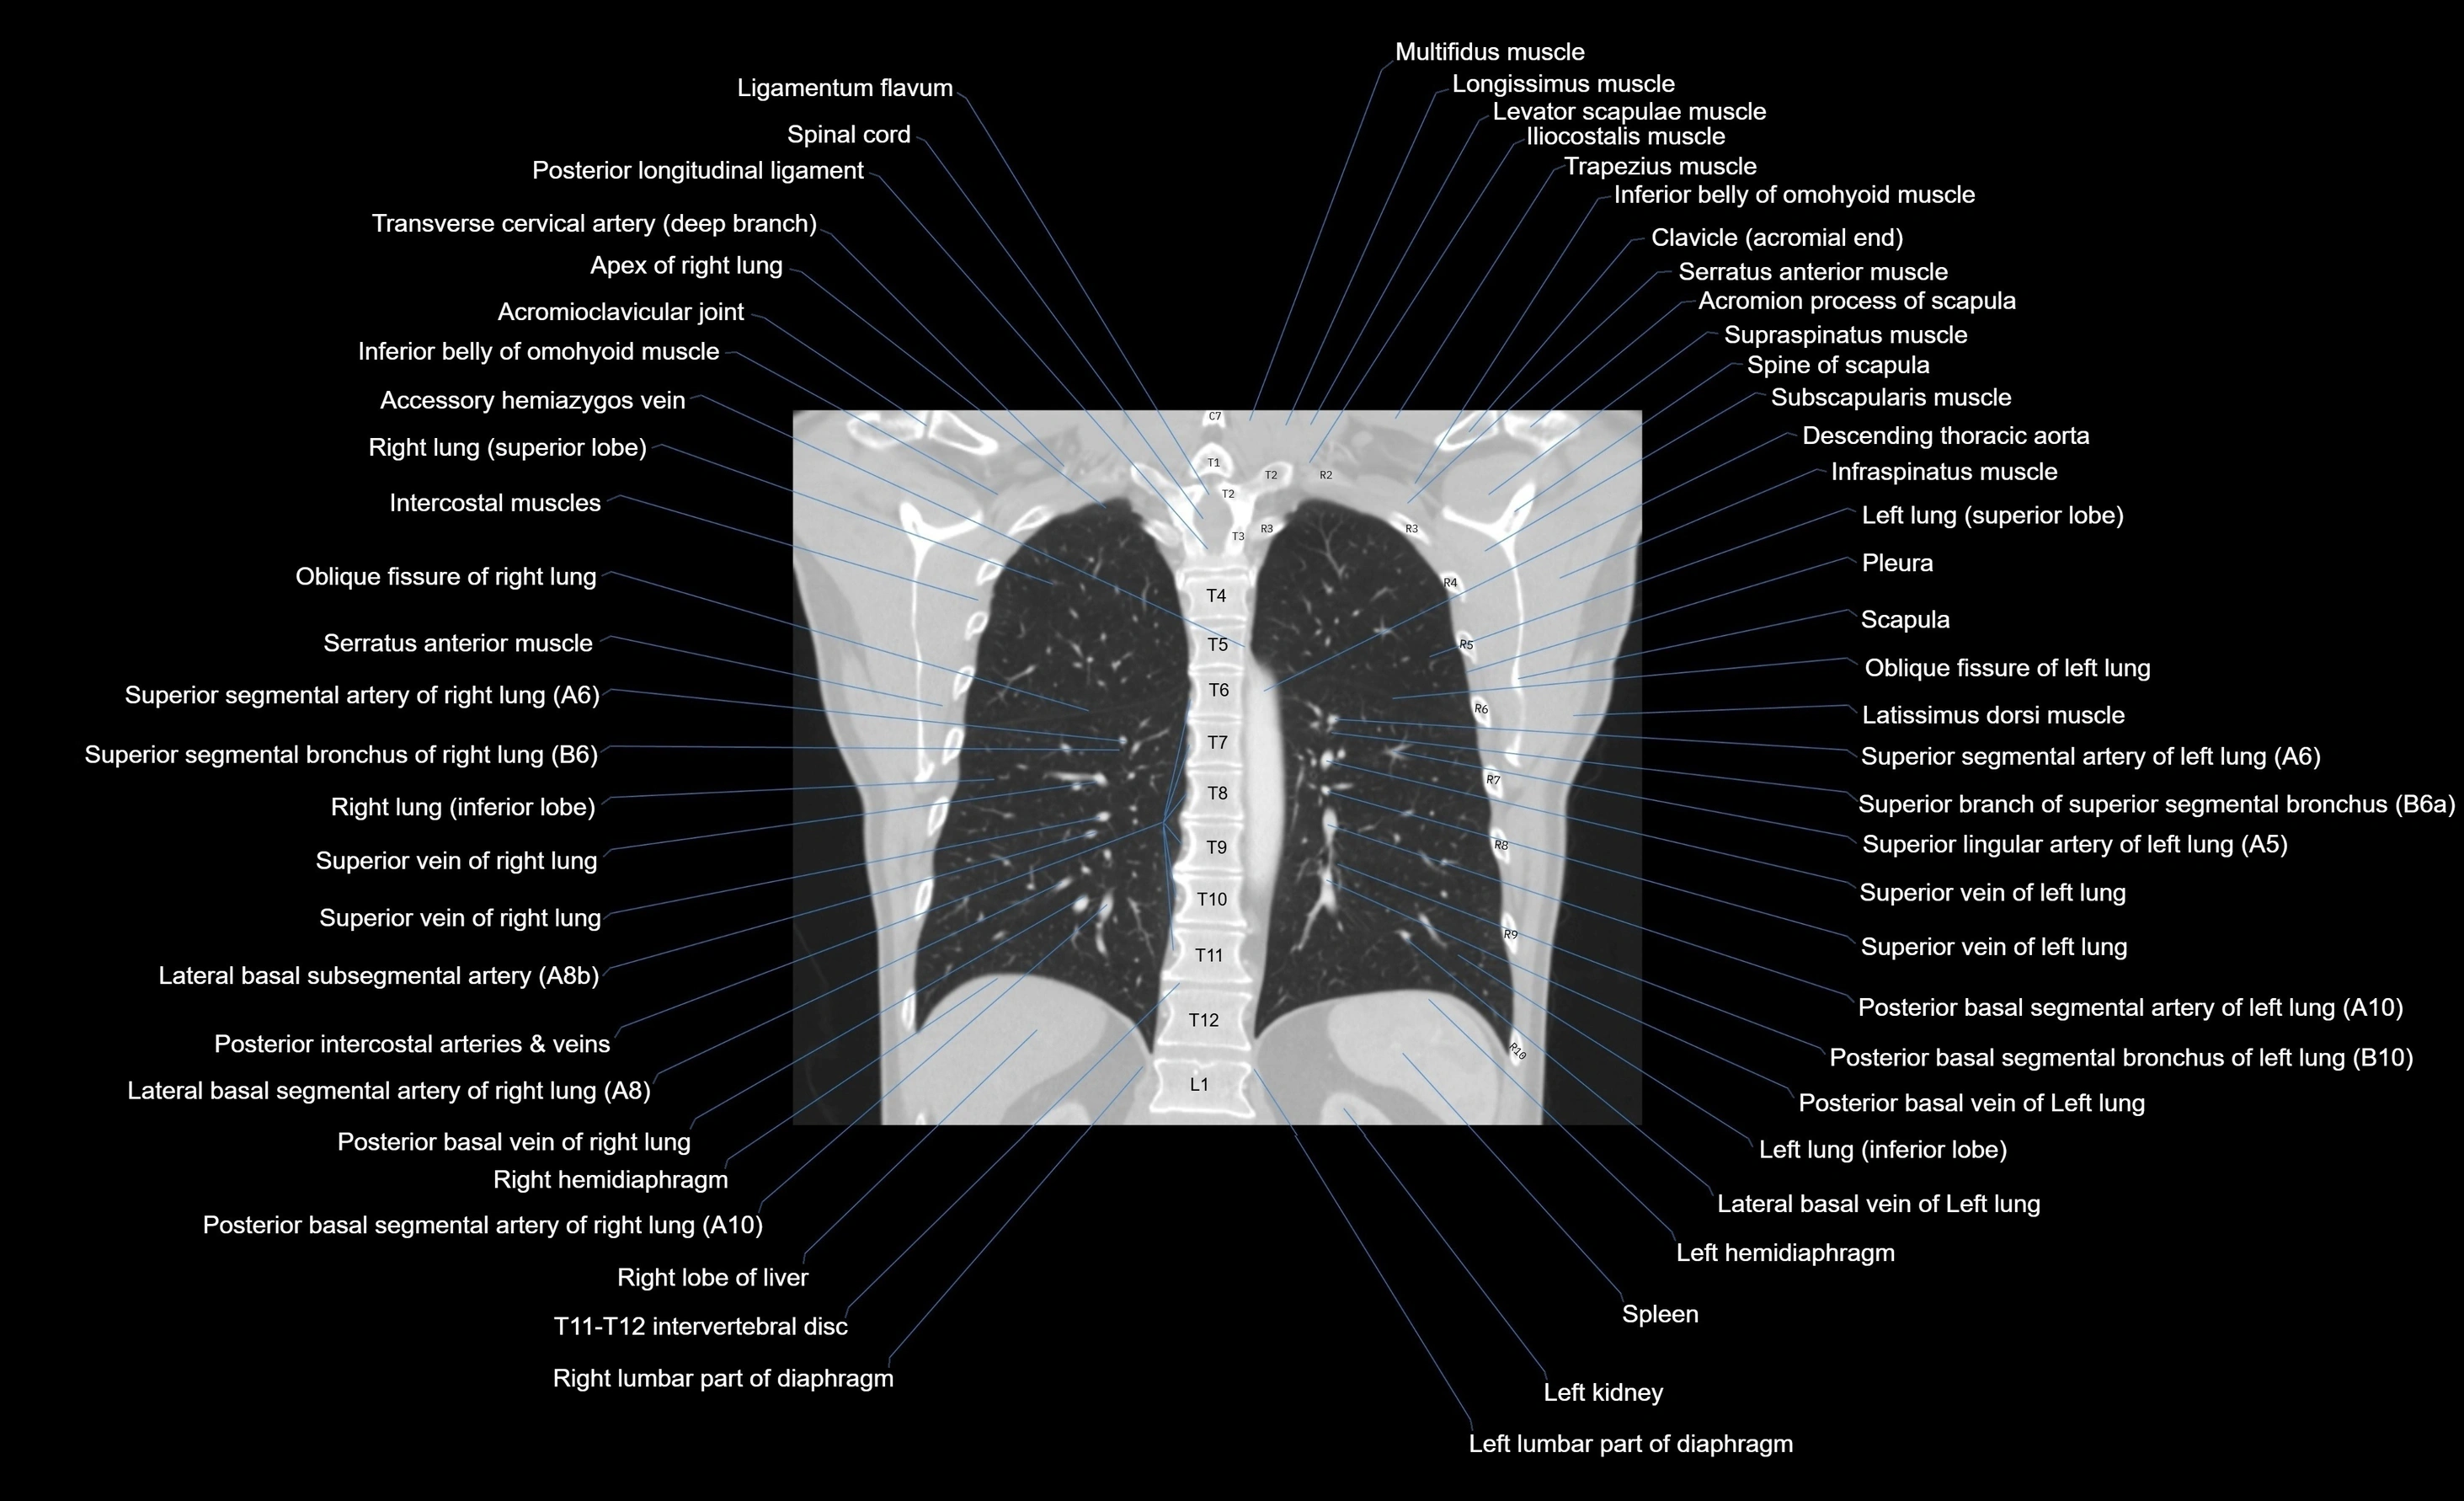

- Acromioclavicular joint

- Acromion process of scapula

- Apex of right lung

- Descending thoracic aorta

- Infraspinatus muscle

- Latissimus dorsi muscle

- Levator scapulae muscle

- Ligamenta flava (Ligamentum flavum)

- Lumbar part of diaphragm

- Multifidus muscles

- Oblique fissure of left lung

- Oblique fissure of right lung

- Pleura

- Posterior basal segmental artery of left lung

- Posterior basal segmental artery of right lung

- Posterior basal segmental bronchus of left lung (B10)

- Posterior basal segmental bronchus of right lung (B10)

- Posterior basal vein of left lung

- Posterior basal vein of right lung

- Scapula

- Serratus anterior muscle

- Serratus posterior inferior muscle

- Serratus posterior superior muscle

- Spine of scapula

- Spleen

- Subscapularis muscle

- Superior segmental artery of left lung

- Superior segmental artery of right lung

- Superior segmental bronchus of right lung (B6)

- Superior vein of left lung

- Superior vein of right lung

- Supraspinatus muscle

- T (Thoracic spine)

- Trapezius muscle